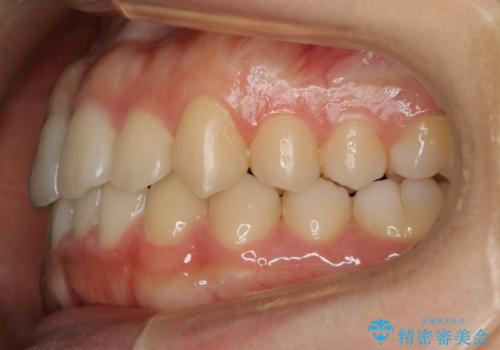

【非抜歯】すきっ歯と噛み合わせの治療

- 上の前歯のすきっ歯と下の前歯のガタつきを主訴にご来院されました。

噛み合わせの改善も同時に進めつつ、主訴の部分も効率的に治していくためマウスピース装置でゴムかけを行いながら治療を進めていきました。

正中離開(すきっ歯)

真ん中の歯が左右に開いてしまい隙間ができてしまう状態を「正中離開」といい、俗にすきっ歯と呼ばれています。

隙間を埋めていく方向に歯を移動させることで改善していくケースが多く、比較的治りやすい不正咬合のひとつとされています。

しかしながら、歯が捻じれていたり、噛み合う歯との位置関係によっては治療が難しくなる場合があります。